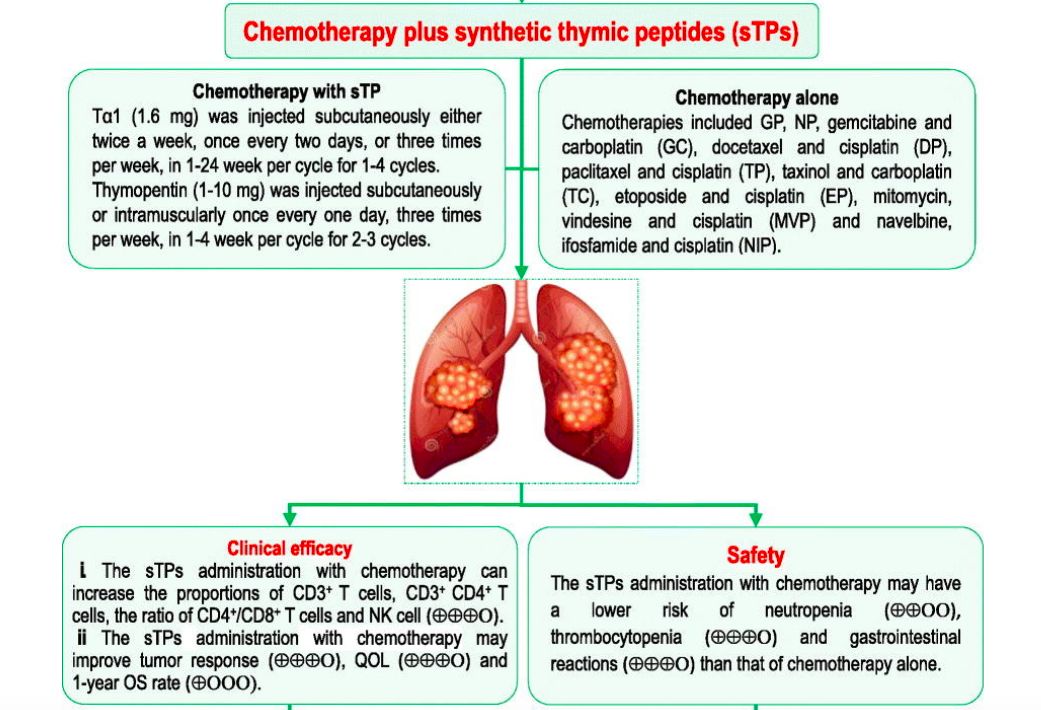

颇具争议的增强免疫力的胸腺肽辅助药物,肺癌患者应该怎么用?...

颇具争议的增强免疫力的胸腺肽辅助药物,肺癌患者应该怎么用?...